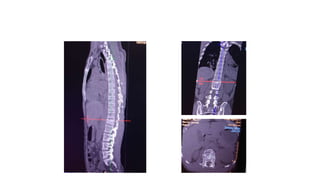

Burst fracture of L1 vertebrae

Saggital, Coronal and Axial

• 52.

Burst fracture ofL1 vertebrae Saggital, Coronal and Axial